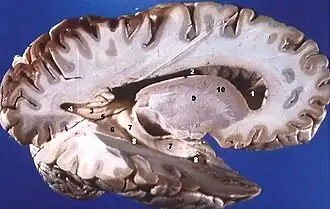

Hémisphère droit d'un cerveau humain disséqué à la suite d'une coupe sagittale, révélant la substance grise dans la partie externe et la substance blanche dans la partie interne.

La substance blanche est une catégorie de tissu du système nerveux central, principalement composé des axones myélinisés des neurones. Elle relie différentes aires de la substance grise où se situent les corps cellulaires des neurones. Elle constitue la partie interne du cerveau et la partie superficielle de la moelle épinière.